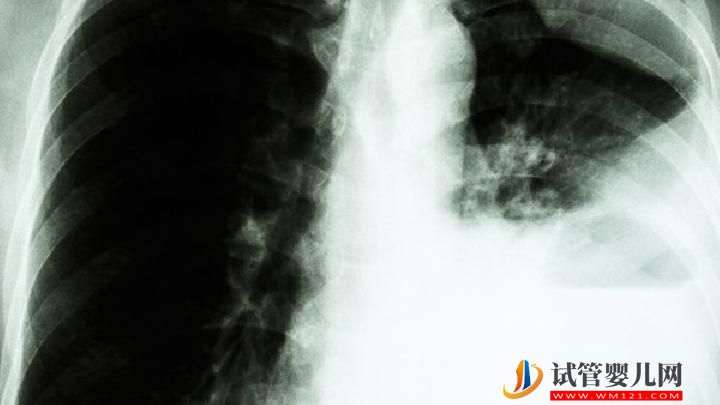

肺癌患者可以过性生活吗?你知道为什么肺癌不传染吗?

为什么肺癌不传染?